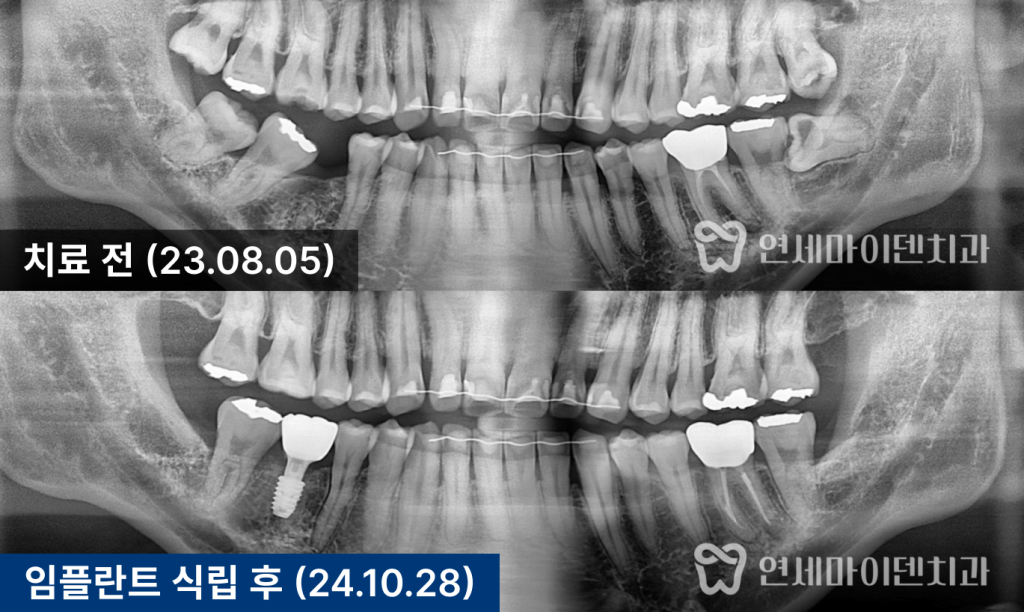

파노라마 사진을 통해 확인한 결과,

- 6번 치아 부위의 공간이 심하게 좁아져 있었으며

- 위아래 사랑니는 모두 자라 있었고, 일부는 충치가 심했습니다.

3개월 경과 시점에서는

점점 어금니가 세워지며, 임플란트 공간이

서서히 확보되는 변화가 확인되었습니다.

부분 교정 7개월차 경과

7개월 차에는 쓰러졌던 7번 어금니가

거의 정상 각도로 회복되었으며,

6번 어금니 임플란트를 위한 공간이 충분히 확보되었습니다.

임플란트 식립

공간 확보 후에는 6번 어금니 부위에 임플란트를 식립하였고,

약 2~3개월간의 안정화 기간을 거쳐

뼈와 임플란트가 단단히 결합되었습니다.